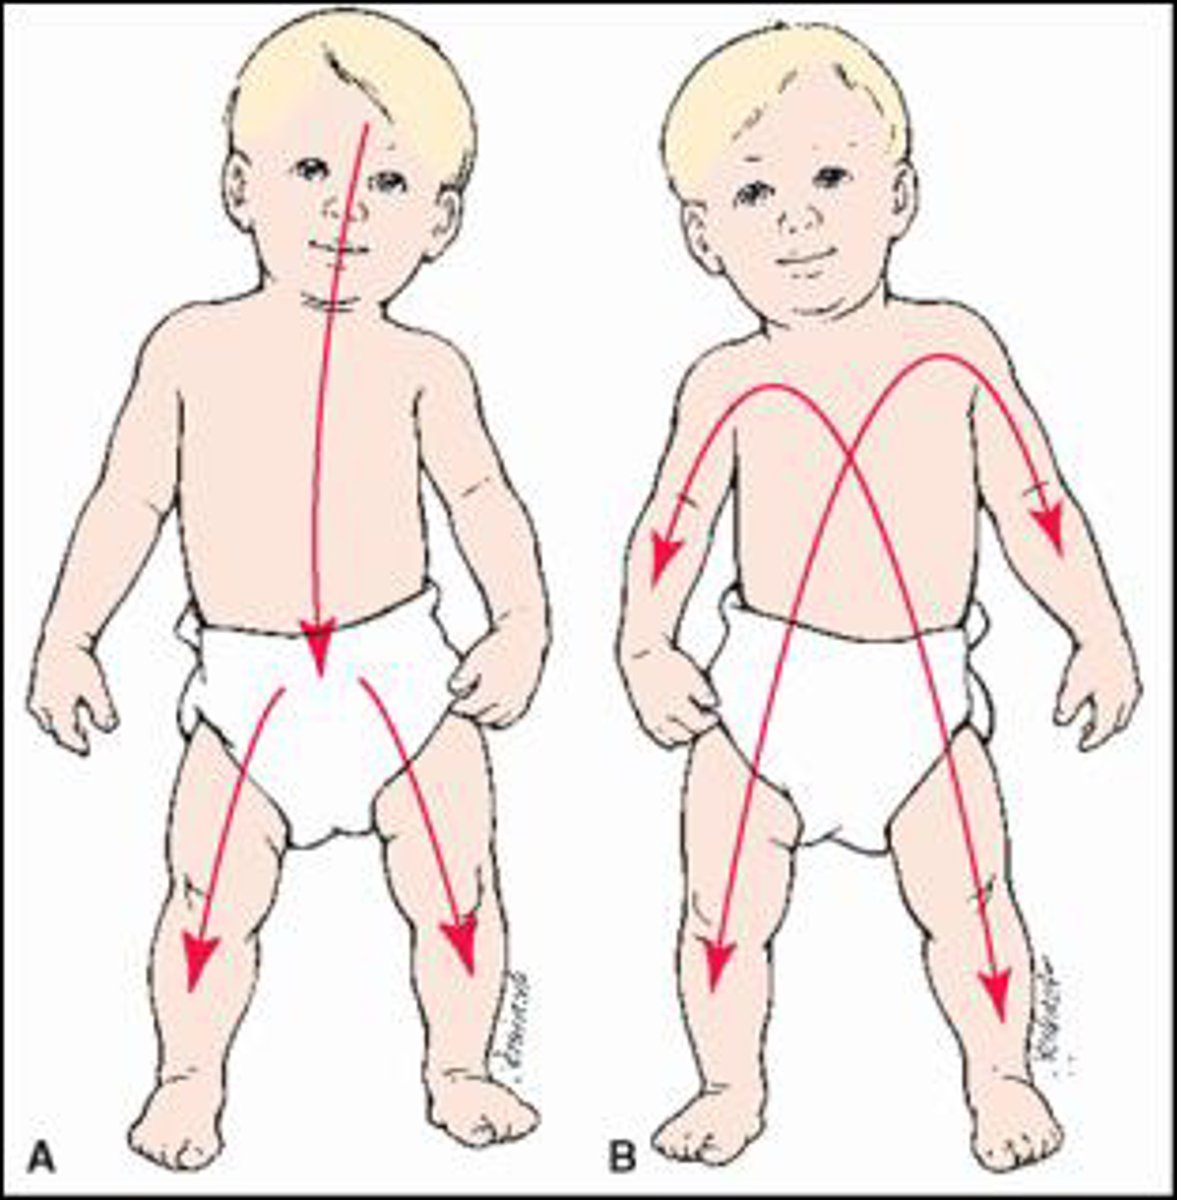

Do Gross Motor Developmental Milestones develop cephalocaudally or proximal to distal?

Cephalocaudal (head to toes)

Do Fine Motor Development Milestones develop cephalocaudaully or proximal to distal?

Proximal to distal (shoulder --> finger)

In the picture...

A = cephalocaudal (Gross motor)

B = proximal to distal (Fine motor)